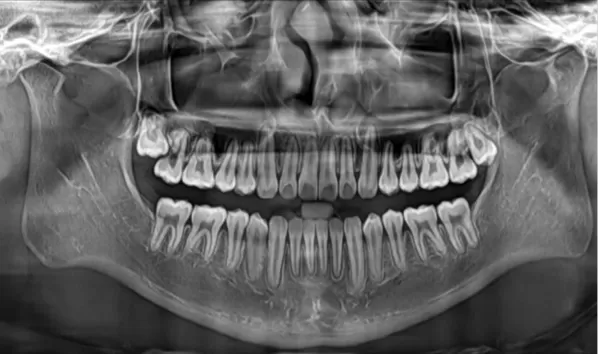

X-rays before treatment

[Panoramic Radiography/Lateral Cephalogram]